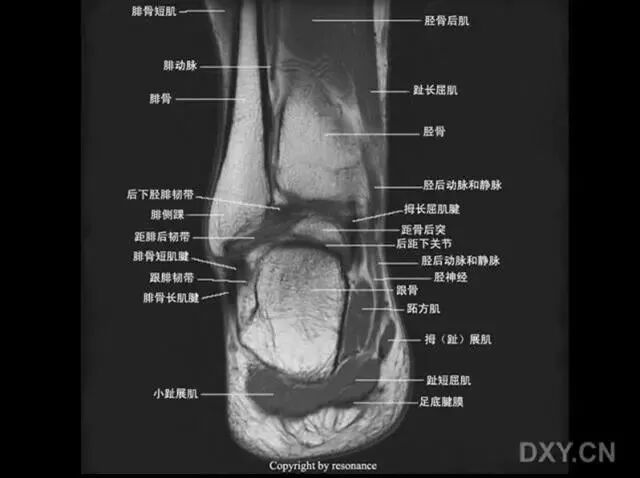

扭伤机制

距骨在踝穴内有无倾斜,会通过影响关节面接触面积而影响关节所受应力的大小。有轻度倾斜,关节面所受到的应力会因为承重面积变小而明显增加。

距骨体前宽后窄,当踝关节背屈时,其宽部进入踝穴,能防止踝关节向后脱位;当跖屈时,其窄部进入踝穴,则关节不稳,易向侧方活动。

旋后扭伤分类

依据损伤结构,分为如下三类:

Ⅰ度:ATFL损伤;

Ⅱ度:ATFL+CFL损伤;

Ⅲ度:ATFL+CFL+PTFL损伤。